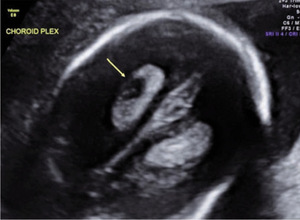

Torbiel splotu naczyniówkowego jest małą, wypełnioną płynem strukturą w obrębie naczyniówki bocznych komór mózgu płodu. W obrazie ultrasonograficznym torbiele splotu naczyniówkowego pojawiają się jako bezechowe struktury w echogenicznej naczyniówce (ryc. 1). Torbiele splotu naczyniówkowego mogą być pojedyncze lub mnogie, jedno- lub obustronne i zazwyczaj mają poniżej 1 cm średnicy. Stwierdzane są u około 1-2% płodów w drugim trymestrze ciąży i występują w równym stopniu u płodów płci męskiej i żeńskiej.1